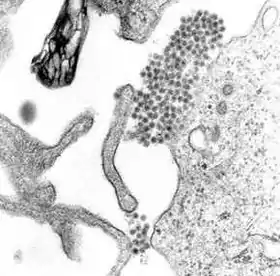

Există și situații în care țânțarii pot lua virusul denga de la oameni. Dacă o femelă țânțar înțeapă o persoană infectată cu virusul denga, țânțarul respectiv poate contracta virusul. La început, virusul trăiește în celulele din sistemul digestiv al țânțarului. După 8-10 zile, virusul se răspândește la nivelul glandelor salivare care au rolul de a secreta saliva (sau „sputa”). Aceasta înseamnă că saliva produsă de țânțar este infectată cu virusul denga care este transmis ulterior la om prin înțepătura de țânțar. Se pare că virusul nu afectează în niciun fel țânțarii infectați, aceștia continuând să fie purtători ai virusului denga pe toată durata vieții lor. Virusul denga este răspândit în special de țânțarul Aedes aegypti. Acest lucru se întâmplă datorită faptului că acest țânțar preferă să trăiască în apropierea așezărilor umane și să se hrănească cu sângele oamenilor, nu cu cel al animalelor.[17] În plus, el preferă să își depună ouăle în rezervoarele de apă construite de oameni.